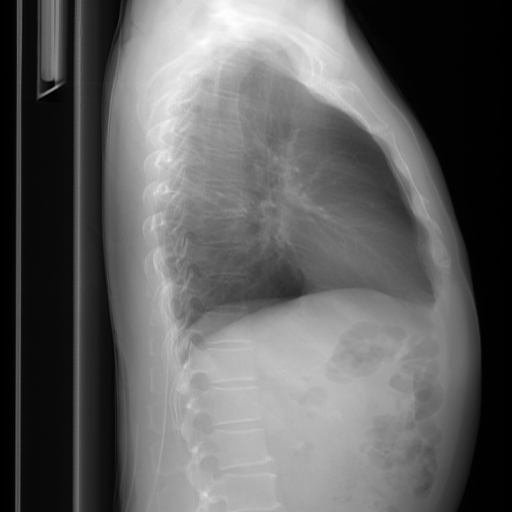

In conventional chest X-Ray exams, the erect patient is positioned between an X-Ray tube and a detector. The collected data by the detector is then used to create a comprehensive image. The main distinctions in positioning (such as anteroposterior (AP) and posteroanterior (PA), both of which we refer to a Frontal, or lateral (L)), are related to which view enables the most insight.

We compare our projected X-Rays with samples from the OpenI dataset for frontal and lateral views in Figure 5. The differences in the frontal view are due to the different positioning of the shoulder girdle. In the X-Rays, the arms are usually placed alongside the body, while in the projected images, the arms are raised due to the nature of the CT scan. In the lateral view, the X-Rays show a more comprehensive range of orientation and pose. However, the projected images, typically taken while the patient is lying down, result in similar poses between the different images. This leads to visual differences between images of female patients in both frontal and lateral views, such as the third column and second row of real X-Ray images and the first column and second row of projected images.